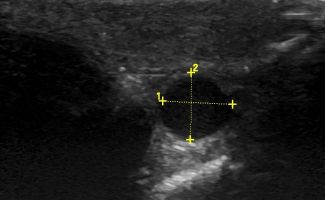

Πολλές αλλοιώσεις και παθήσεις μπορούν να απεικονιστούν υπερηχογραφικά και να μελετηθούν αξιόπιστα με τη βοήθεια του Έγχρωμου Doppler και της Ελαστογραφίας .

- Όγκοι των σιελογόνων αδένων ή της γλώσσας